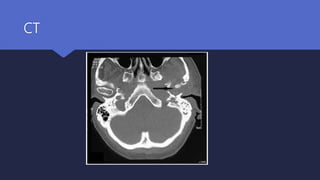

 Ct scan :

Defines the anatomical extent of the disease

Remains the initial investigation of choice

CT

Diagnosis Radiological investigations  Ctscan : Defines the anatomical extent of the disease Remains the initial investigation of choice  MRI scan Useful for assessing the initial severity of the disease Excellent at delineating the extent of soft tissue disease Intracranial complications

• #18 CT scan showing the soft tissue obliterating left external auditory canal left mastoid, infra-temporal fossa, skull base and involving the left TMJ.

• #19 Axial CT scan of a 63-year-old patient who has diabetes and left malignant otitis externa showing bony erosion of the posterior external auditory canal and mastoid cortex